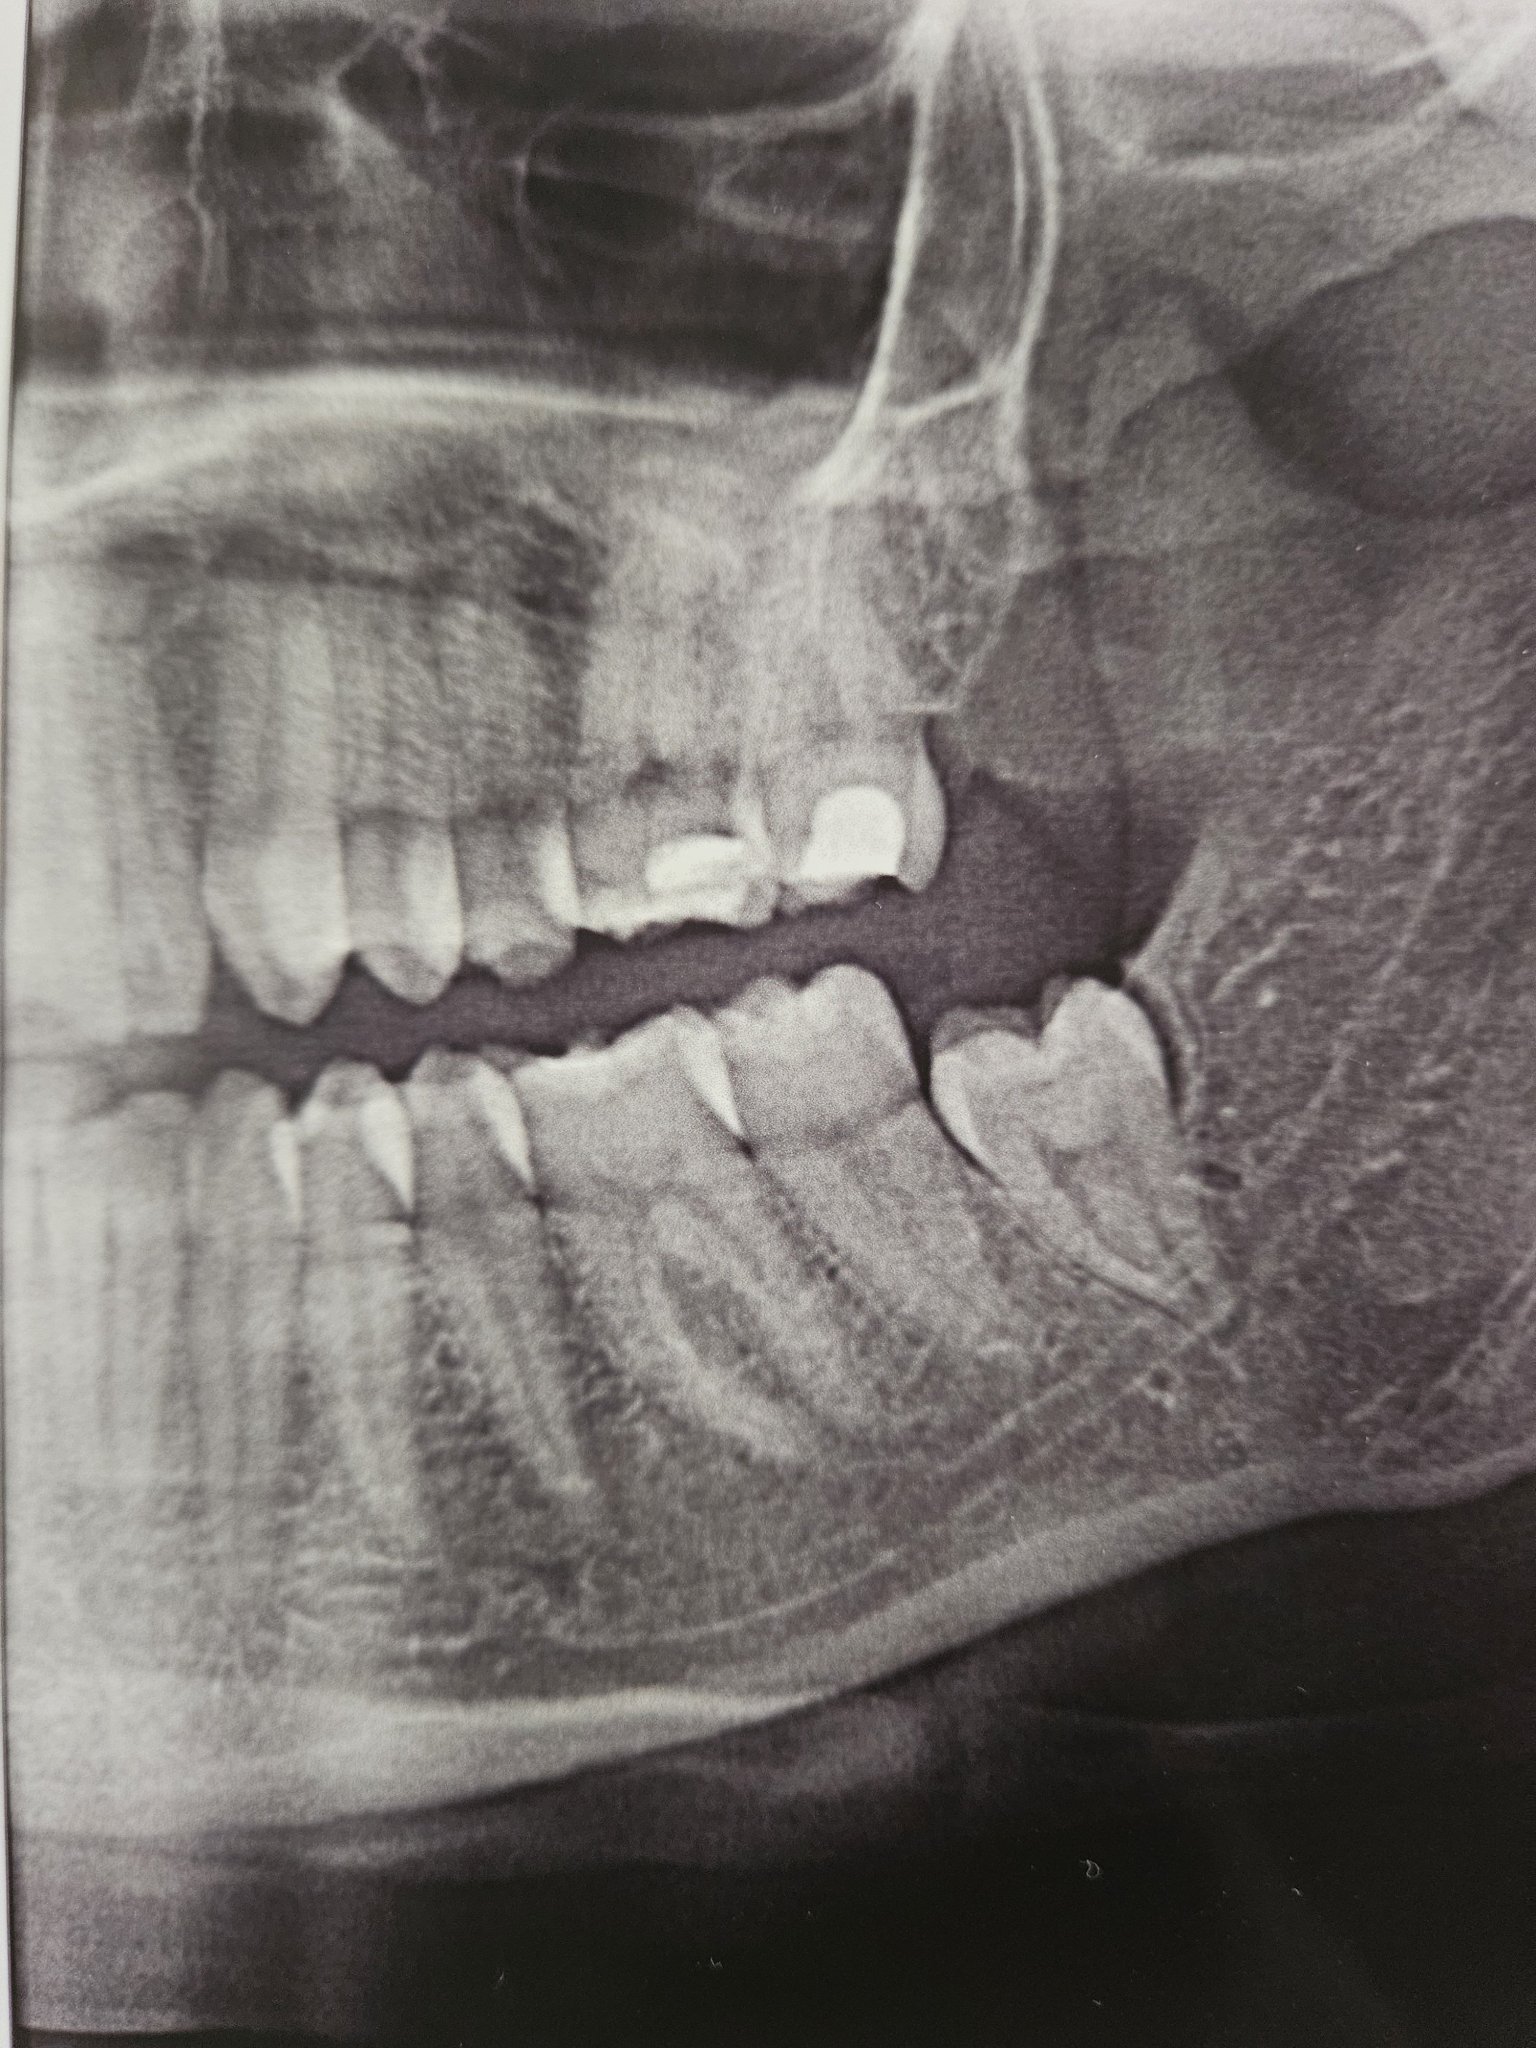

• Мнения: 1

Здравейте, дали някой, който е запознат може да ми каже дали лесно ще се извади долен десен мъдрец, трябва ли да се реже кост, той е пред пробиване , но все още не е пробил , почнах да имам големи болки в главата и мнение за др Геков от ЕО Дент , имате ли или за някой, който би се справил?

Аз препоръчвам д-р Величков от СвеДент. Иначе мъдреца изглежда нормално и не би трябвало да ива проблем. Моят например освен, че не беше пробил и беше в костта беше странично т.е колонката буташе корените на предния зъб а корените на мъдреца бяха насочени към гърлото. Така, че при вас всичко е до рутина. Даже и не е счупен и с пломби мъдреца което също би било усложнение при ваденето. Успех!